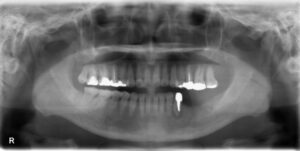

上顎前歯1本欠損症例

BEFORE AFTER 46歳女性/上1本欠損/インプラント埋込手術 【治療内容】 右上の側切歯の被せものが土台から外…